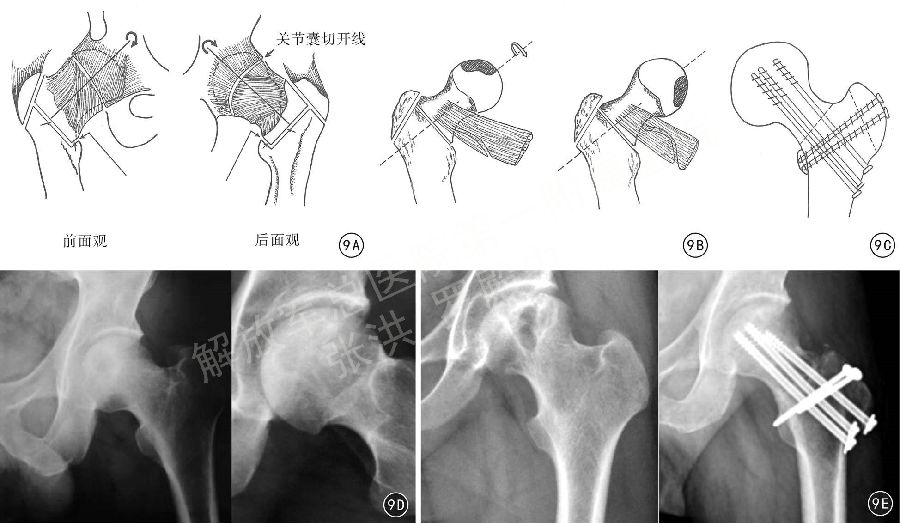

Sugioka 于1978年设计了针对早期股骨头坏死的股骨颈基底部旋转截骨术,后经多人改良,但保髋的临床效果参差不齐(图9A~9C)。张洪等 在对股骨头血运充分掌握的基础上, 再次进行了改良, 对北美骨循环协(Association Research Circulation osseous, ARCO)II期和IIIA、IIIB期的患者,先通过SHD行股骨颈软组织瓣延长,再进行股骨颈基底部旋转截骨手术,使股骨头可以向前旋转、也可以向后旋转90°~180°,将股骨头坏死区域旋转到非负重区,取得更大更灵活的旋转角度,避免股骨头血运进一步损害,避免股骨头的塌陷,从而取得长期的保髋治疗效果(图9D、9E)。

图9 早期股骨头坏死的手术治疗方式,9A Sugioka 股骨颈基底部旋转截骨术,9B 改良Sugioka 股骨颈基底部旋转截骨术,9C 笔者对Sugioka 股骨颈基底部旋转截骨手术进行改良,经髋关节外科脱位手术入路行股骨颈软组织瓣延长、股骨颈基底部旋转截骨内固定,9D 患者男,41岁,左股骨头坏死ARCO域B期,术前左髋关节正位、蛙氏位图片摇9E摇患者男,40岁,左股骨头坏死ARCO IIIA期,改良Sugioka股骨颈基底部旋转截骨术,术前、术后X线片